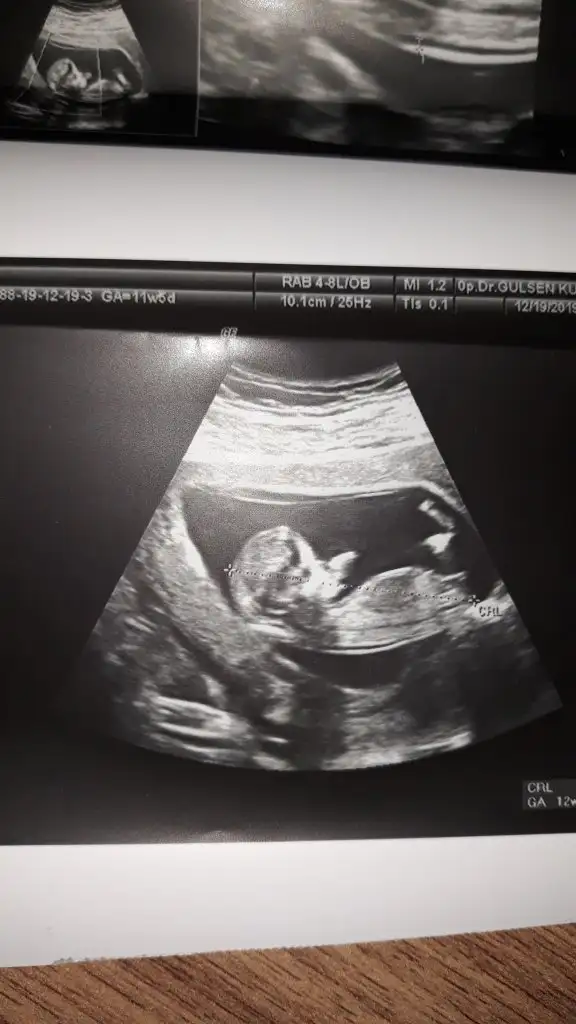

Merhaba bayanlar ben yine doktora gittim ama öğrenemedik cinsiyeti. Bu da son usg. 12h5d

Eklentiler

• IMG_20191221_171735.webp

IMG_20191221_171735.webp

10,7 KB · Görüntüleme: 59